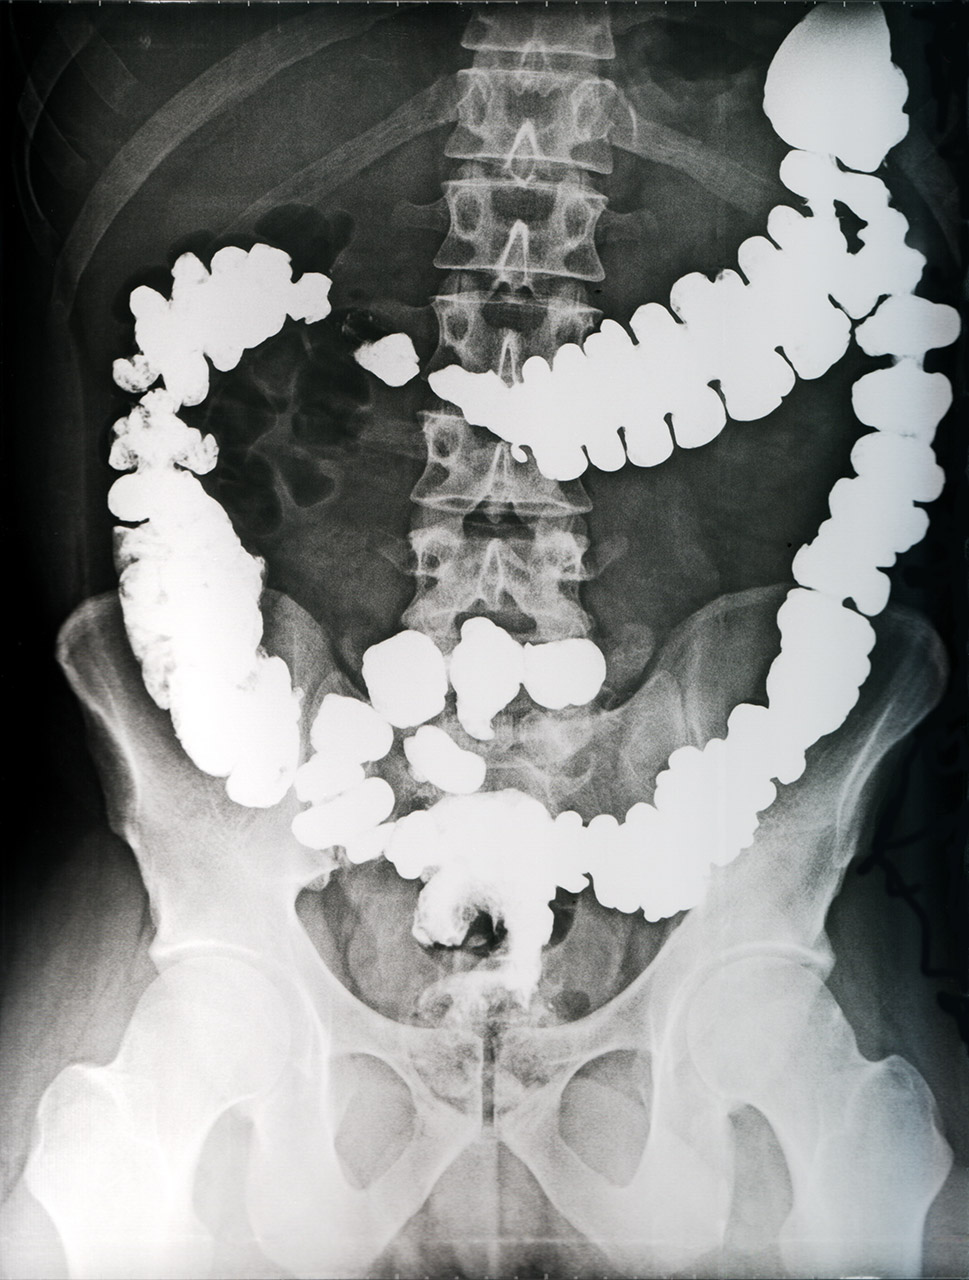

Prior to examination by computer tomography, the doctor administers a contrast medium solution to the patient.

Isotopes with a short half-life (primarily iodine 131I and technetium 99mTc) are used in medicine. They are used for contrast imaging, for identification of an organ’s functionality, or as a marker. They disintegrate in the patient’s body very quickly.